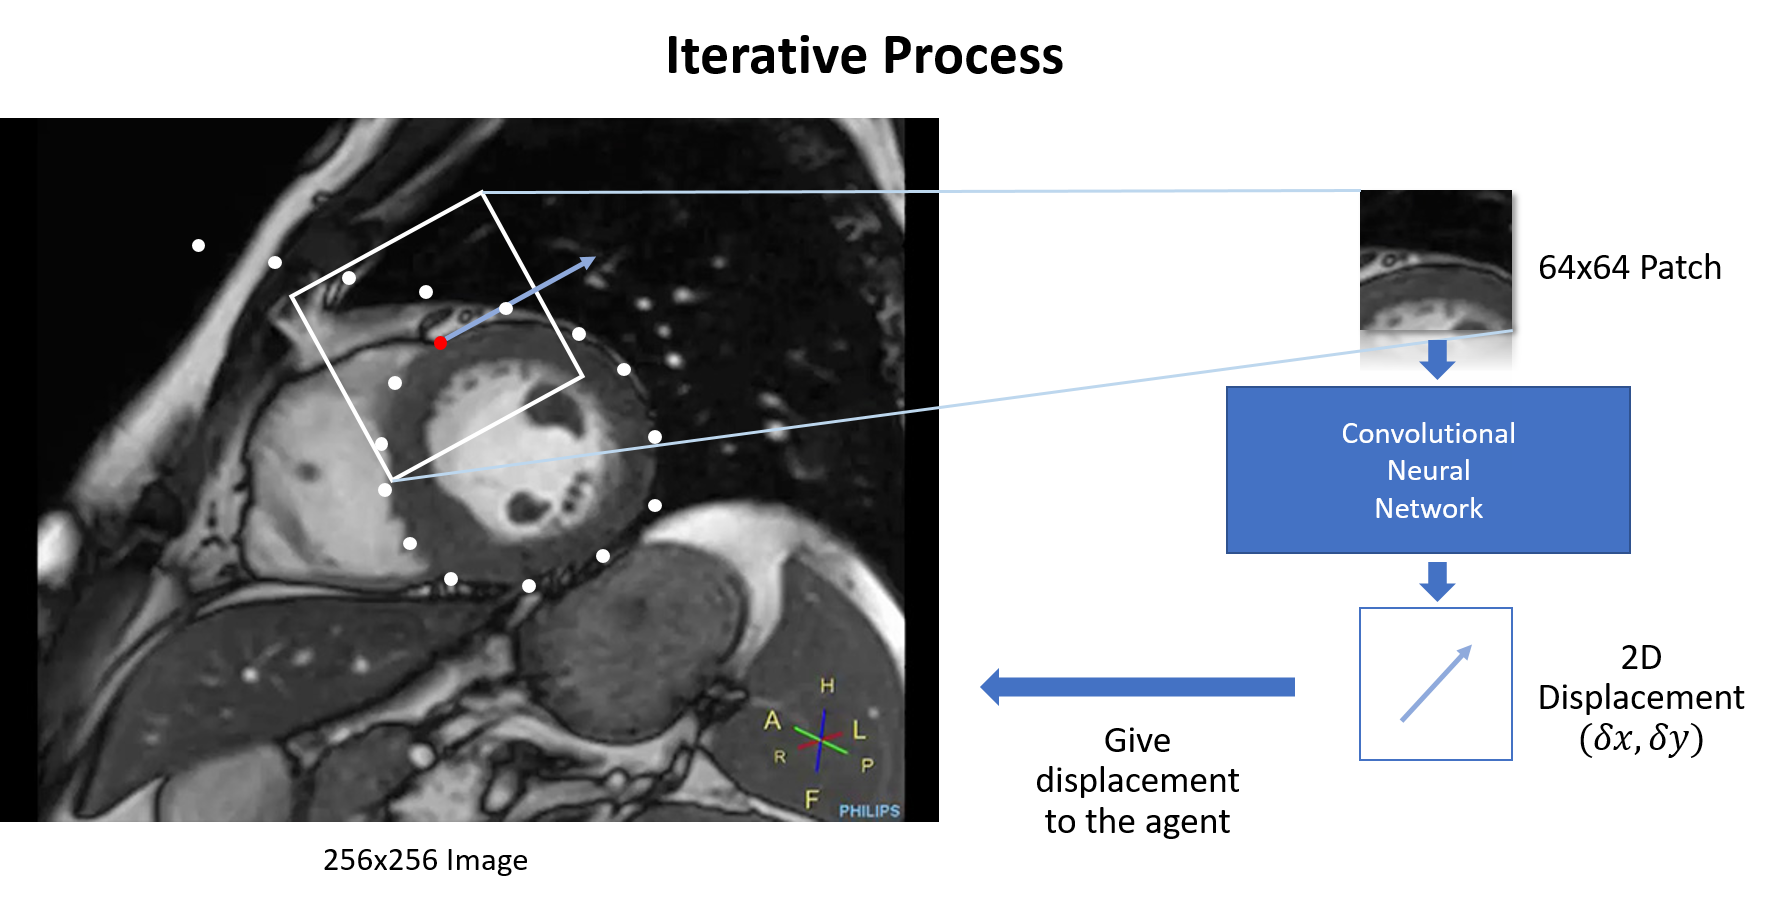

Figure 1: The red dot denotes the current position of the agent. In each time step, the DPM extracts a locally oriented patch from the original image. The extracted patch will be fed into a CNN to predict the next step displacement for the agent. After a finite number of iterations, A trajectory will be created by the agent. The magnitude of the Poincaré map is used to determine the final periodic orbit which is coincident with the boundary around the ROI.

As shown in Fig 1, The DPM uses a CNN-based policy model, trained on locally oriented patches from manually segmented data, to navigate an agent over a cardiac MRI image (256x256) using a locally oriented square patch (64x64) as its input. The agent creates a trajectory over the image tracing the boundary of the LV – no matter where the agent starts on the image. A crucial prerequisite of this methodology is the creation of a vector field whose limit cycle is equal to the boundary surrounding the ROI. This can be seen in Fig 5(b). In the following sections we will discuss the DPM methodology in detail, namely 1) the creation of a customized dynamic (i.e. a vector field) with a limit cycle around the ROI of the manually delineated images. 2) The creation of a patch-policy predictor. 3) The stopping criterion using the Poincaré map.